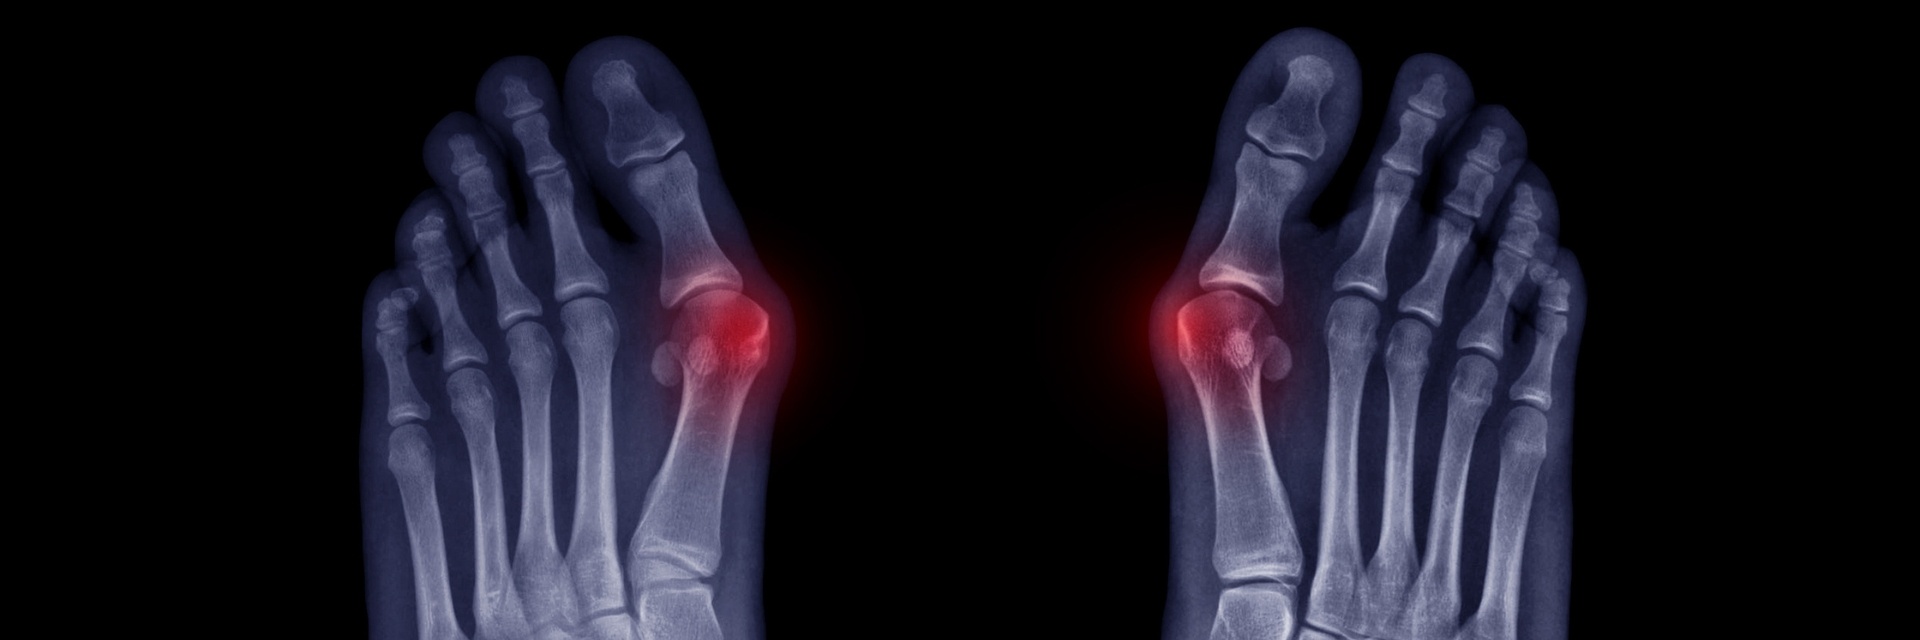

Minimally Invasive Osteotomy for Bunion Correction: Surgical Technique and Results